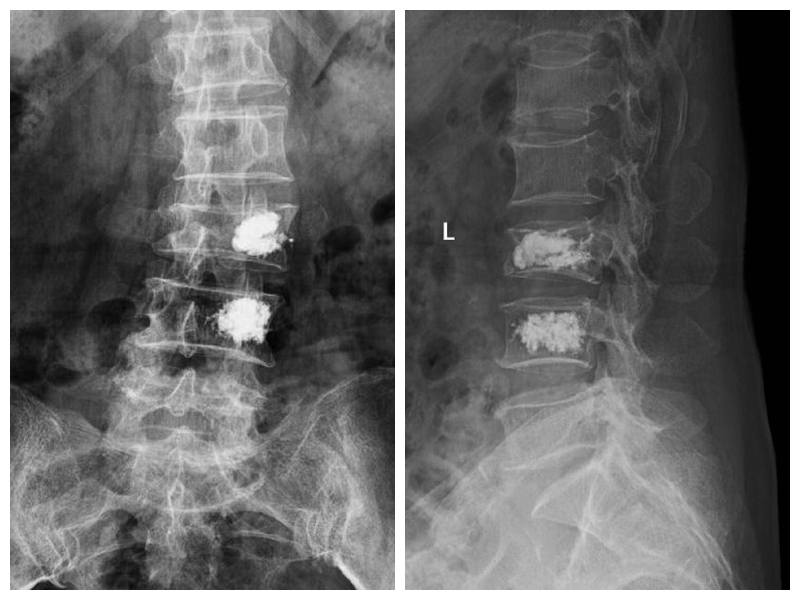

典型病例:患者劉**,女,70歲,因“在家滑倒摔傷腰背部疼痛活動(dòng)受限2天”步行入院。查體:腰3、4棘突壓痛,椎體及椎旁壓痛明顯,雙下肢肌力、感覺正常。

術(shù)后第1天患者下地行走,腰痛明顯緩解。(骨科二區(qū) 孫進(jìn))